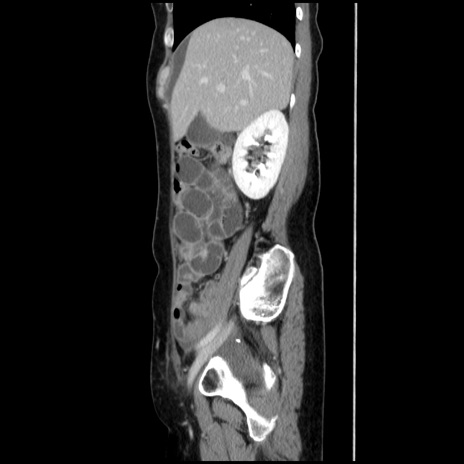

症例32(矢状断像)

【症例】40歳代 女性

【主訴】上腹部痛、嘔気・嘔吐

【現病歴】約9時間前頃から急に上腹部痛、嘔気、嘔吐が出現。改善しないため救急要請。

【既往歴】子宮頚癌(広汎子宮全摘術、放射線療法)、腸閉塞

【身体所見】腹部:平坦、軟、腸雑音亢進、上腹部を中心に腹部全体に圧痛あり。

【データ】WBC 8400、CRP 0.03